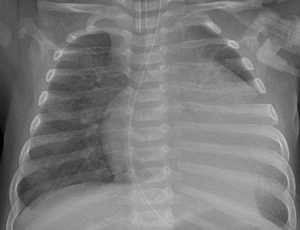

Röntgenbild von einem drei Monate alten, beatmeten Kind mit Myokarditis. Links ist das Herz massiv vergrößert